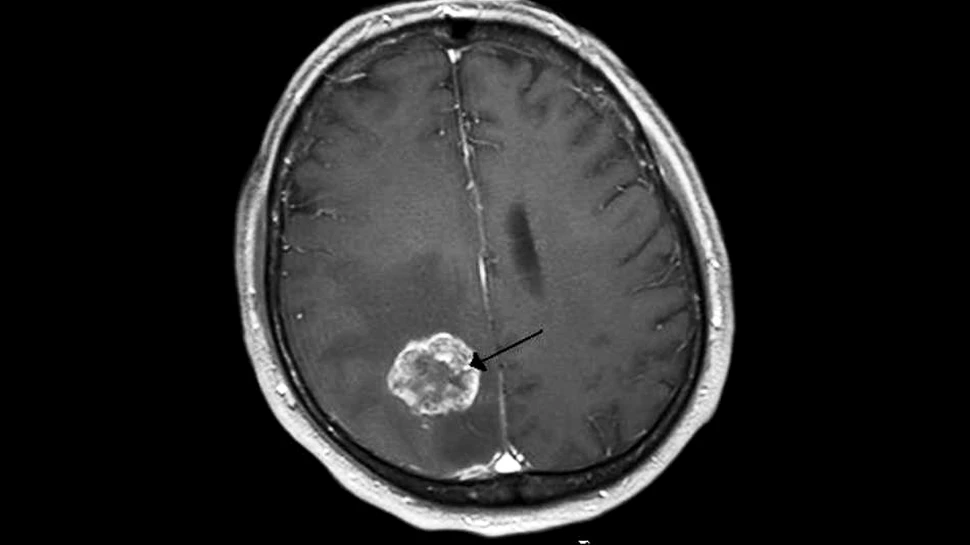

CMV are un rol central în dezvoltarea anumitor forme de cancer, precum cel la creier, sân, intestin sau prostată – cancere care, în Marea Britanie, de pildă, provoacă anual decesul a aproape 43.000 de persoane.

Recent, cercetătorii de la Institutul Karolinska din Suedia au descoperit că, dacă acest virus este tratat cu unele medicamente analgezice, antiinflamatoare şi antivirale obişnuite, rata de creştere a tumorilor poate scădea cu până la 72%.